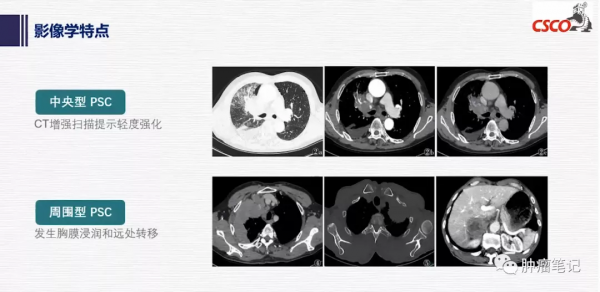

肺肉瘤樣癌(PSC)約佔肺癌的0.1%-0.4% ,佔非小細胞肺癌的1%。多發生於中老年吸菸男性,且呈年輕化趨勢。在影像學上多變現為周圍型肺癌,並且對放化療不敏感,預後很差。

PSC在CT影像上具有一定特點,表現為腫瘤體積巨大;直徑多數>3cm,有的可達到18 cm;多為單發,中心型或外周型,圓形,密度均勻,邊緣光滑,可有毛刺或分葉,鈣化少見;增強CT呈環形或斑片狀強化;胸壁侵犯和(或)胸腔積液徵象。